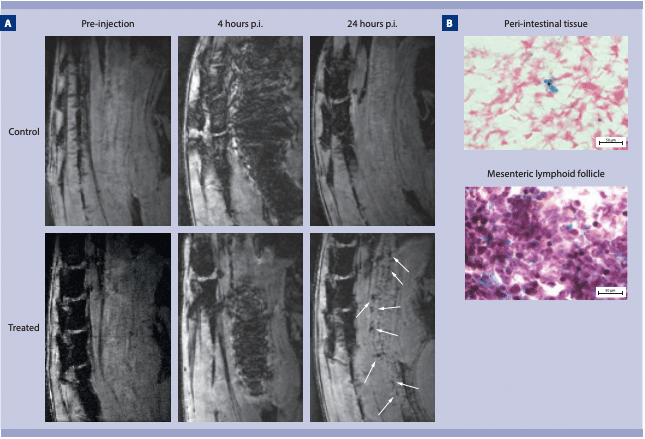

Medilumine offers the Viscover™ portfolio of preclinical MRI contrast agents, designed to enhance image quality and expand the capabilities of animal MRI studies. The portfolio includes GadoSpin™ gadolinium chelates for high-performance vascular, organ, and tumor imaging, and FeraSpin™ iron oxide nanoparticles, which are widely used for cell labeling and in vivo cell tracking by MRI. Together, Viscover MRI agents support applications such as cell tracking, tumor and vascular imaging, cardiovascular studies, magnetic resonance angiography (MRA), and therapy response monitoring, enabling more informative and translational preclinical imaging.